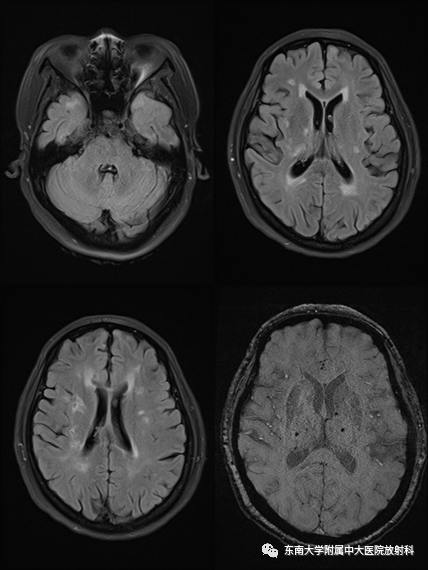

【PPT】伴有皮质下梗死和白质脑病的常染色体显性遗传性脑动脉病(CADASIL)

女,51岁

主诉:反复发作性头晕2年余,再发加重1周

相关病史:患者2年前无明显诱因下出现头晕,表现为头重脚轻,伴有头痛,无高血压、高血脂、冠心病病史,体格检查及实验室检查均未见明显异常